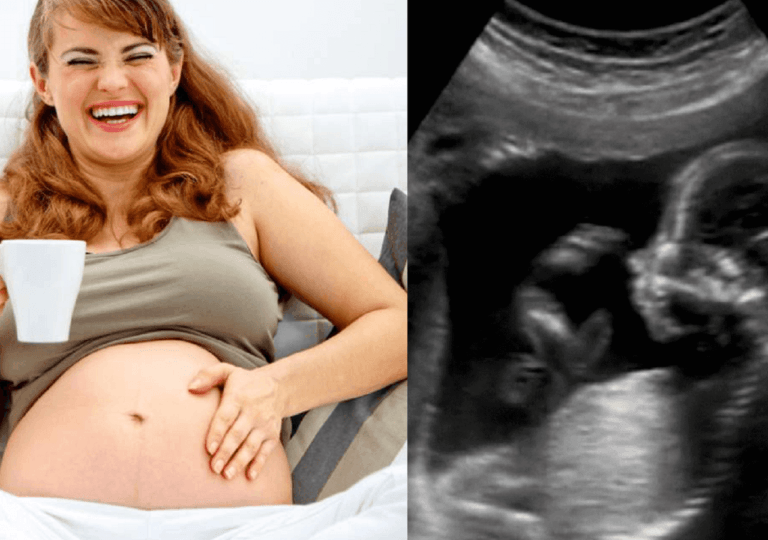

Όλοι έχουμε γελάσει με την ψυχή μας! Με γέλια ικανά να θεραπεύσουν την ψυχή μας και να φέρουν δάκρυα ευτυχίας στα μάτια μας! Και το καλύτερο; Αποδεικνύεται ότι αυτά δεν είναι μόνο υπέροχες στιγμές για μας – είναι και για το αγέννητο μωρό μας!

Σωματικά, το μωρό κινείται πάνω και κάτω όταν γελάει η μητέρα.

«Όταν παρακολουθούμε το έμβρυο στο υπερηχογράφημα και η μητέρα αρχίζει να γελάει, μπορούμε να δούμε το έμβρυο, να είναι ανάποδα στη μήτρα και το κεφάλι να πηγαίνει πάνω κάτω σαν να αναπηδά σε ένα τραμπολίνο» δήλωσε ο Janet DiPietro, από το τμήμα ερευνών του John Hopkins. «Όταν οι μητέρες παρακολουθήσουν στην οθόνη τι γίνεται στη μήτρα τους, γελούν πιο έντονα και το έμβρυο ανεβαίνει και κατεβαίνει ακόμα πιο γρήγορα. Αναρωτιόμαστε αν αυτός είναι ο λόγος για τον οποίο αρέσει στους ανθρωπους το τρενάκι του λούνα παρκ.»

Ο Δρ. DiPietro έχει κάνει πολλές έρευνες για τα έμβρυα. Δώδεκα εβδομάδες πριν γεννηθεί το μωρό, συμπεριφέρεται ήδη σαν νεογέννητο. Αυτό σημαίνει ότι το γέλιο μας επηρεάζει τα συναισθήματά του καθώς και την κίνηση.